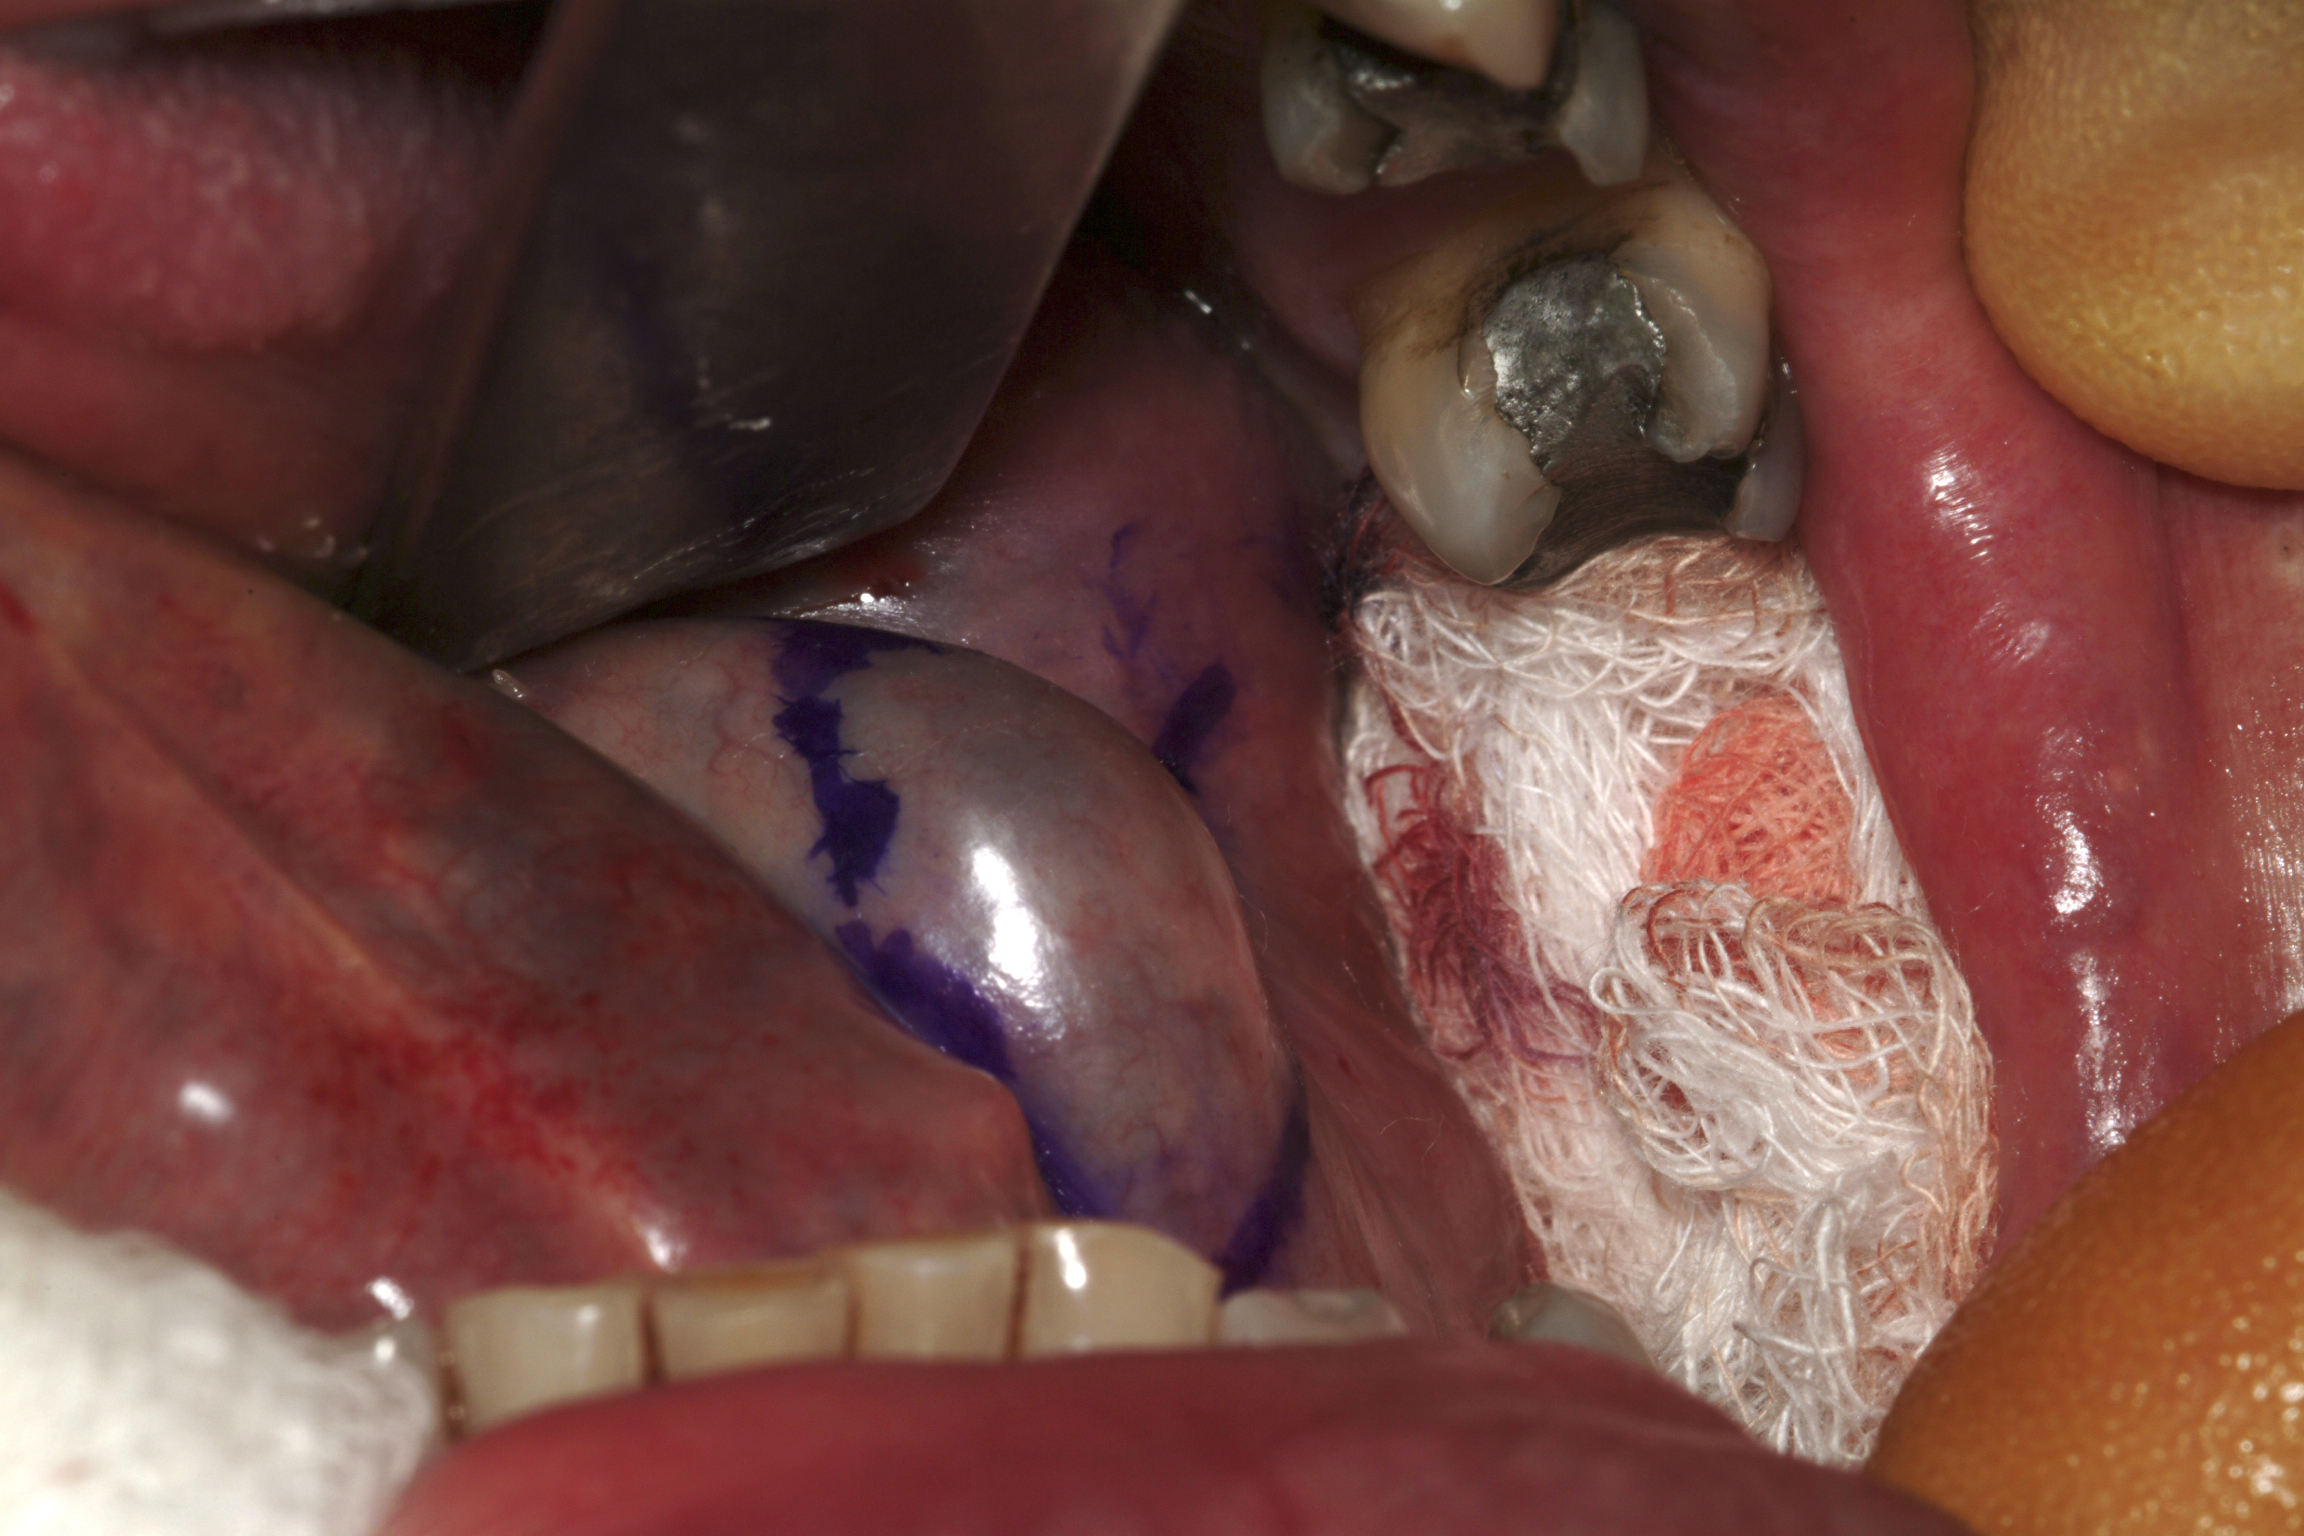

Ranula is a mucous extravasation cyst at the floor of the mouth and will reform if the associated sublingual gland is not removed (see Figure 2).

Figure 2: A ranula marked out for excision with the associated sublingual gland. The submandibular duct should be preserved.

There is a risk for an altered sensation of the anterior (front) two thirds of the tongue and bleeding from the thin-walled veins that envelope the lingual nerve.

Excision of the sublingual gland is performed in conjunction with excision of the ranula, under general anaesthesia. Haemostasis (stopping bleeding) is helped by infiltrating adrenaline solution and meticulous bipolar diathermy. The position of the submandibular duct can be found by identifying its opening, and a small cuff of mucosa around the opening should be incised both to identify and to allow mobilisation of the duct (see Figure 3). This procedure retains adequate drainage for the submandibular gland, which does not need to be removed.